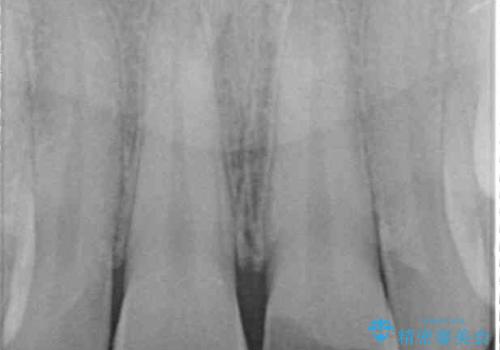

痛みを感じており、歯の欠けている状況から、神経組織のダメージも想定されました。

外傷歯は、将来的に歯根吸収を起こす可能性があるため、定期的なレントゲン撮影により経過観察が必要となります。